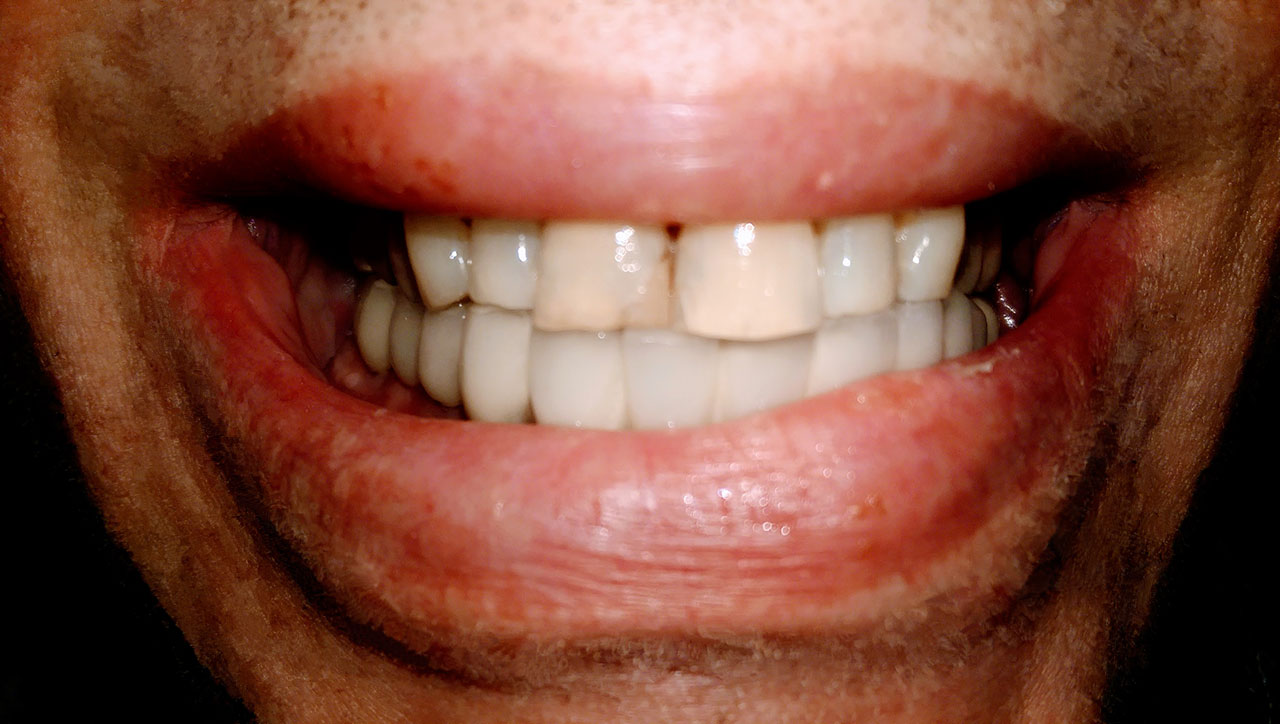

Teljes alsó,felső állcsont helyreállítása azonnal

terhelhető implantátumokkal és porcelán hidakkal.

Teljes alsó, felső állcsont rehabilitáció azonnal terhelhető implantátumokkal és porcelán hidakkal.

Csontritkulás, cukorbetegség, súlyos fogágybetegség és dohányzás nem befolyásolja a sikerességét.